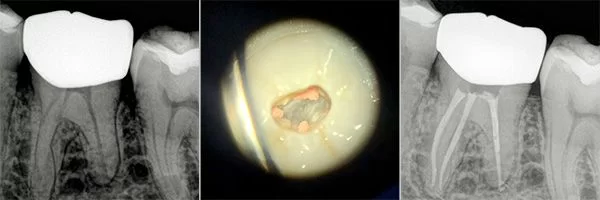

Root Canal in Morocco Before and Afters

Certified Endodontists with Microscope and Laser.

Check out our Before and Afters

Root Canals are done by an Endodontist and require the Specialist to make a hole through the enamel and dentin surfaces to gain access to the pulp chamber, where the Endodontist proceeds to remove the pulp, clean the pulp chamber and seal the chamber with gutta-percha. To ensure the long-term success of the tooth after a Root Canal an antibiotic is prescribed and a Post and Core Build-Up and Crown are recommended to prevent fractures or filtration of bacteria to the tooth.

- The dentist uses a drill to access the pulp chamber and related canals of the tooth. This allows inserting specialized dental instruments to clean the pulp chamber and root canals. Then the specialist cleans completely the remaining space and shapes it to make space for a filling. The filling will replace the pulp in the tooth.

A Post & Core Build-Up is a treatment that is done after a Root Canal and is needed to regain stability and tooth structure to that tooth. Once the pulp chambers are cleaned and sterilized a fiber post will be placed into the chamber to help absorb the shock from masticatory forces. The Post also helps to anchor the Core Build Up to the actual tooth.

A Post is a prosthetic device made of the metal alloy used to give strength and support to the toot structure after a Root Canal Therapy was performed and the due restoration is a Crown or a Bridge.

The Core Build-Up, made of composite material, replaces the nerve extracted in the Root Canal Therapy and supports either a Crown or the Retainer for a Bridge.

The Post & Core Build-Up require to give stability to the Crown or Bridge.